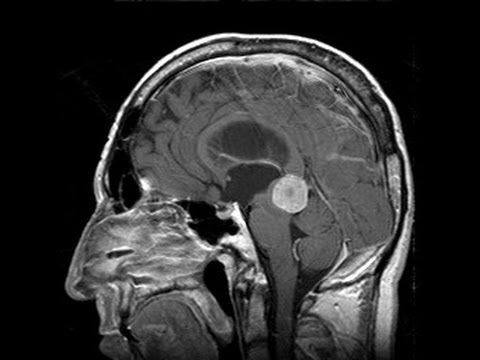

Prof. Dr. Selçuk Yılmazlar, nöroşirürji alanında klinik ve cerrahi uygulamalarıyla ulusal ve uluslararası düzeyde çalışmalar yürütmekte olup, beyin, omurga ve sinir sistemi hastalıklarının tanı ve tedavisinde modern cerrahi yöntemler uygulamaktadır. Uzmanlık alanları arasında beyin tümörleri, bel ve boyun fıtıkları, damar ve sinir cerrahisi gibi birçok alanda hastalarına hizmet sunmaktadır.